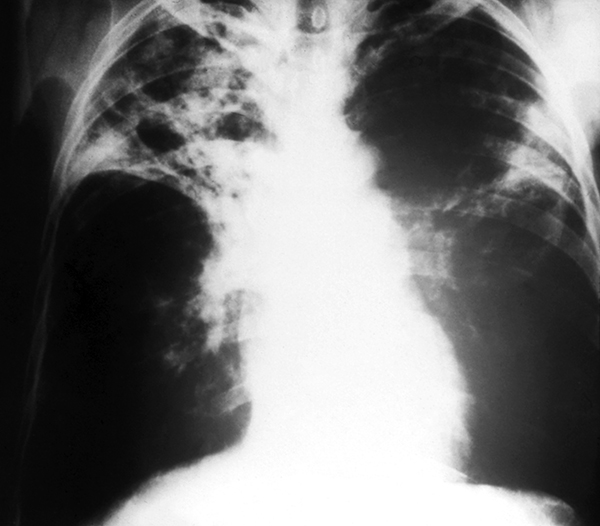

X-ray of lungs with advanced TBX-ray of lungs with advanced TB

CDC

This was the era of reductionist science, people working on model systems, so the major antigen was dinitrophenylated bovine serum albumin [DNP-BSA]. [We were] not aware of anybody dying of bovine serum albumin as a major cause of illness, and here we were working on leprosy bacilli in patients and in animal models, particularly interested in the part of the spectrum where the immune response killed off the bugs but caused tissue damage. That struck me as very odd, and if you think of what tuberculosis is like, it’s a massive immune response to wall off the bacilli that causes a hole in the lung and massive tissue damage in the lung. And while we couldn’t get access to lungs, the principles, I thought, were likely to be very similar.